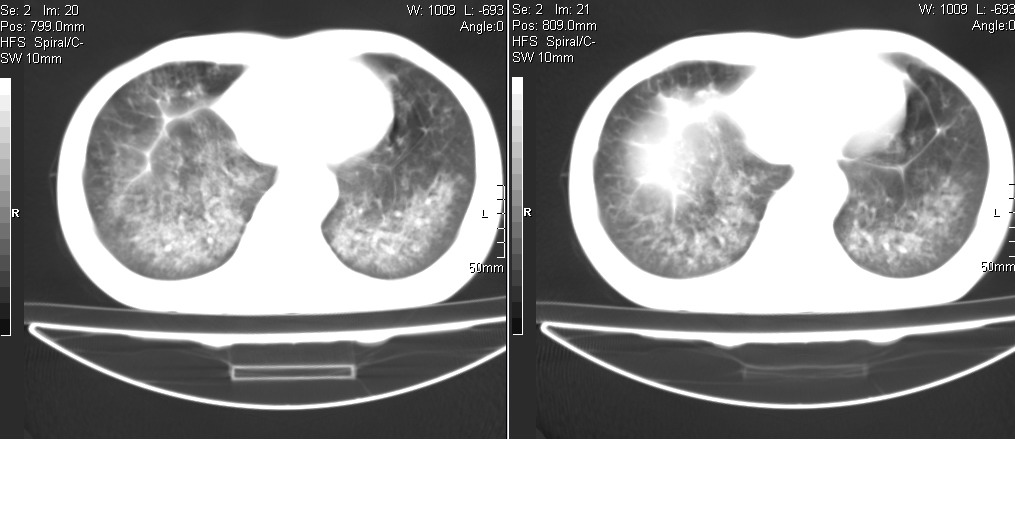

以下是引用光线在2008-5-6 18:36:00的发言:[br]双肺结核(左上肺空洞形成)、间质性改变合并感染,右肺大泡;右侧胸膜增厚。

以下是引用zsl6918在2008-5-7 1:54:00的发言:[br]首先肺泡蛋白质沉着症,其次考虑机遇性感染。